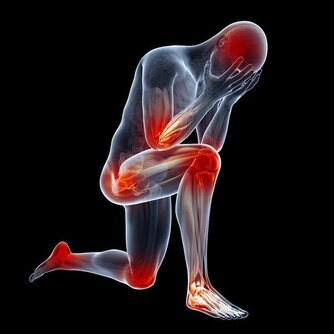

2. 你會出現肌肉痙攣

鉀對肌肉的有效運作至關重要,所以當鉀水平低時,你可能會覺得疼痛,甚至痙攣痛。